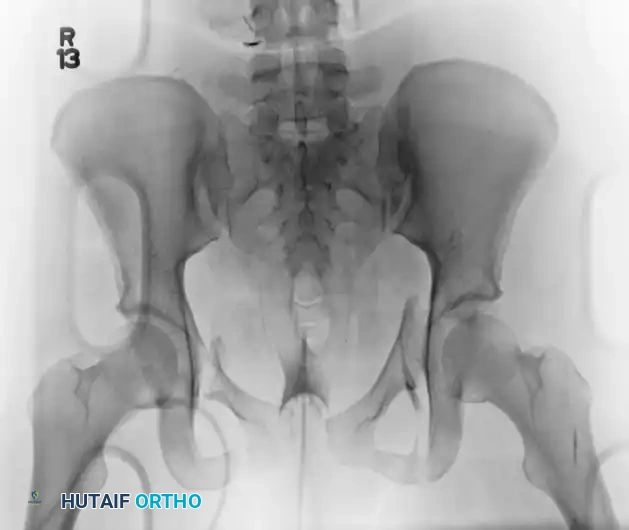

An AP III injury is a completely unstable pelvic ring disruption. It involves complete disruption of the symphysis pubis (or anterior rami) and complete disruption of both the anterior and posterior sacroiliac ligamentous complexes. The hemipelvis is both rotationally and vertically unstable.

Preoperative Evaluation:

The preoperative AP, inlet, and outlet views demonstrate severe pubic diastasis, bilateral pubic rami fractures, and gross widening/displacement of the posterior SI joints.

FIGURE 56-45: Young and Burgess anteroposterior type III (AP III) pelvic ring injury with pubic diastasis and bilateral pubic rami fractures. A-C, Preoperative anteroposterior, inlet, and outlet views, respectively. D, Preoperative CT scan.